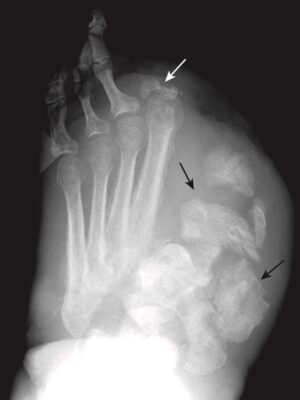

Hình 10. Bệnh khớp Charcot ở bàn chân. Bệnh nhân này trước đó đã được phẫu thuật cắt cụt ngón chân thứ hai (mũi tên trắng) vì hoại thư (gangrene) do tiểu đường, nhưng sự phá hủy và phân mảnh rõ rệt của ngón chân cái và các xương bàn chân là biểu hiện của bệnh thần kinh Charcot (mũi tên đen).